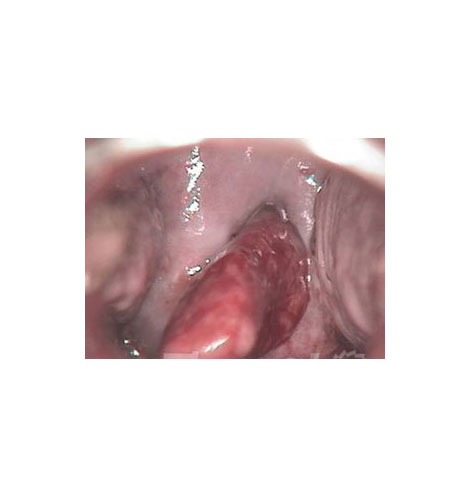

苔藓型外阴白斑